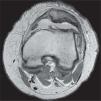

Para obtener imágenes de alta resolución ponderadas en DP con una alta RCR se requiere de TR cercanos a los 6.000ms, un amplio ancho de banda de recepción, cortes finos ajustados a la región a estudiar (patela o cóndilos), campos de visión pequeños y matrices grandes buscando el vóxel isótropo (tabla 2). La mayor resolución espacial y mayor contraste obtenidos con estos ajustes en DP resulta en la adquisición de imágenes muy anatómicas (fig. 7), las cuales facilitan la diferenciación del cartílago articular, en particular, y de todas las estructuras, en general. Con la aplicación de supresión grasa (que además es más sencilla de conseguir y más efectiva a mayor campo magnético8,9) se gana en rango dinámico de contraste. El contraste entre el fluido, hiperintenso, y el cartílago, de intensidad de señal media, facilita la observación de la superficie de este, así como posibles grietas o defectos en su espesor. La aplicación de TR muy largos es de gran importancia para incrementar este contraste.